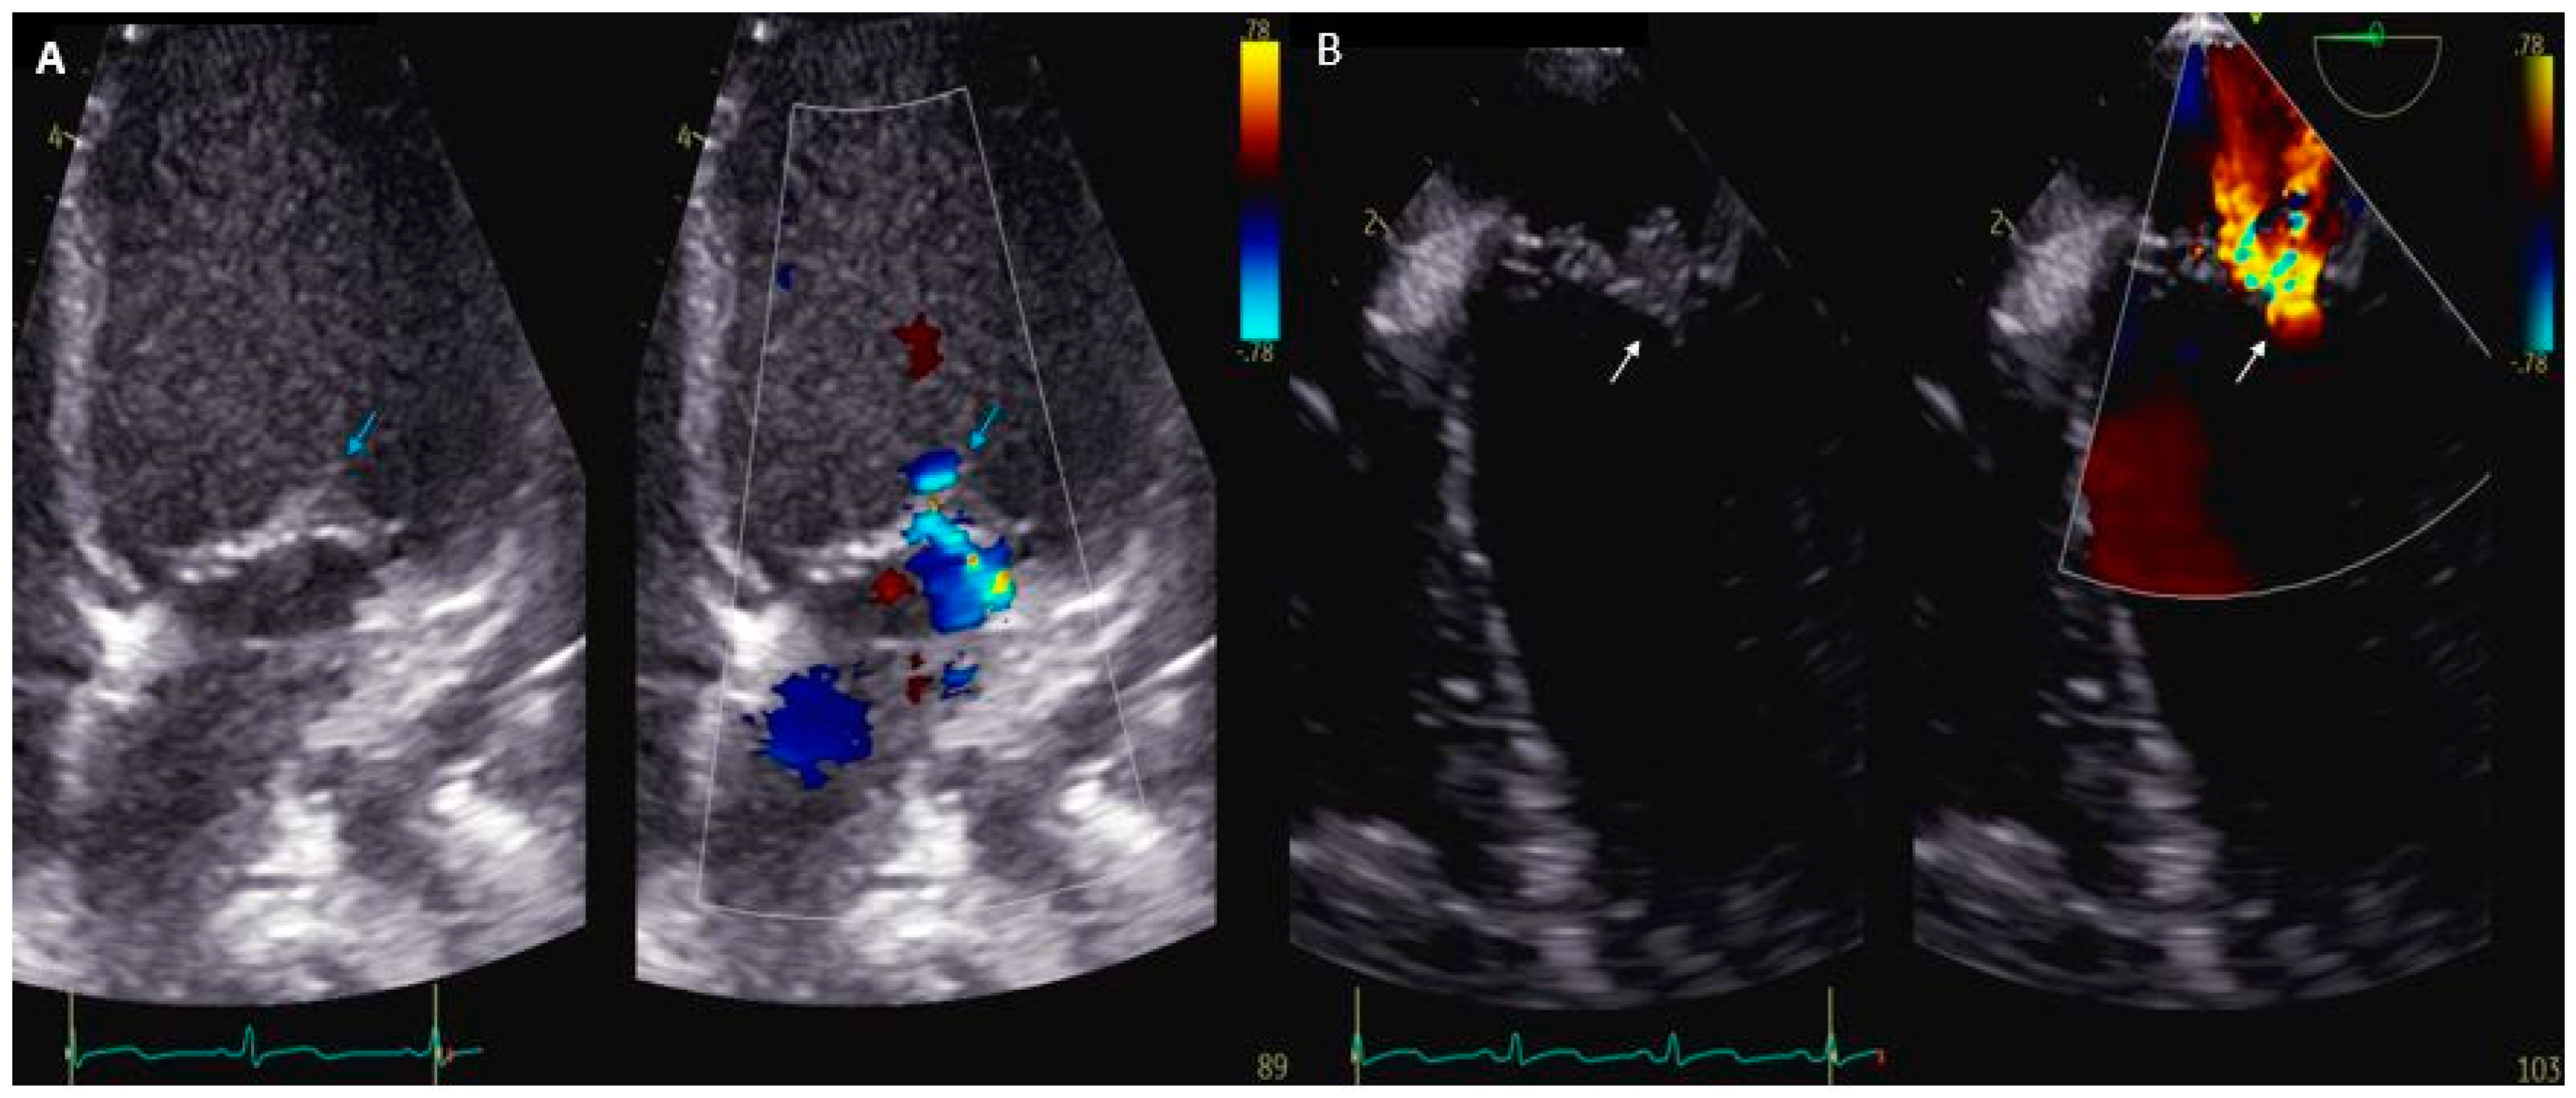

- Joye, R.; Ceroni, D.; Beghetti, M.; Aggoun, Y.; Sologashvili, T. Fulminant Infective Endocarditis Due to Kingella kingae and Several Complications in a 6-Year-Old Girl: A Case Report. Front. Pediatr. 2021, 9, 707760. [Google Scholar] [CrossRef] [PubMed]